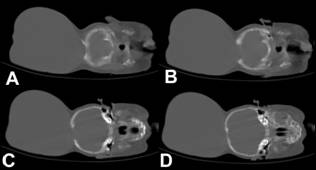

Image

4: Intra-operative photographs showing operative steps (B) small amount of the

CSF was let out through a small opening in the sac, (C) note the reduction in

the size of swelling, (D) sac was opened, (E) base of sac was defined, note the

presence of large vessels near to the opening in the skull, (F and G) redundant

brain tissue was excised while preserving the large vessels, (H and I) dura and

skin were closed.